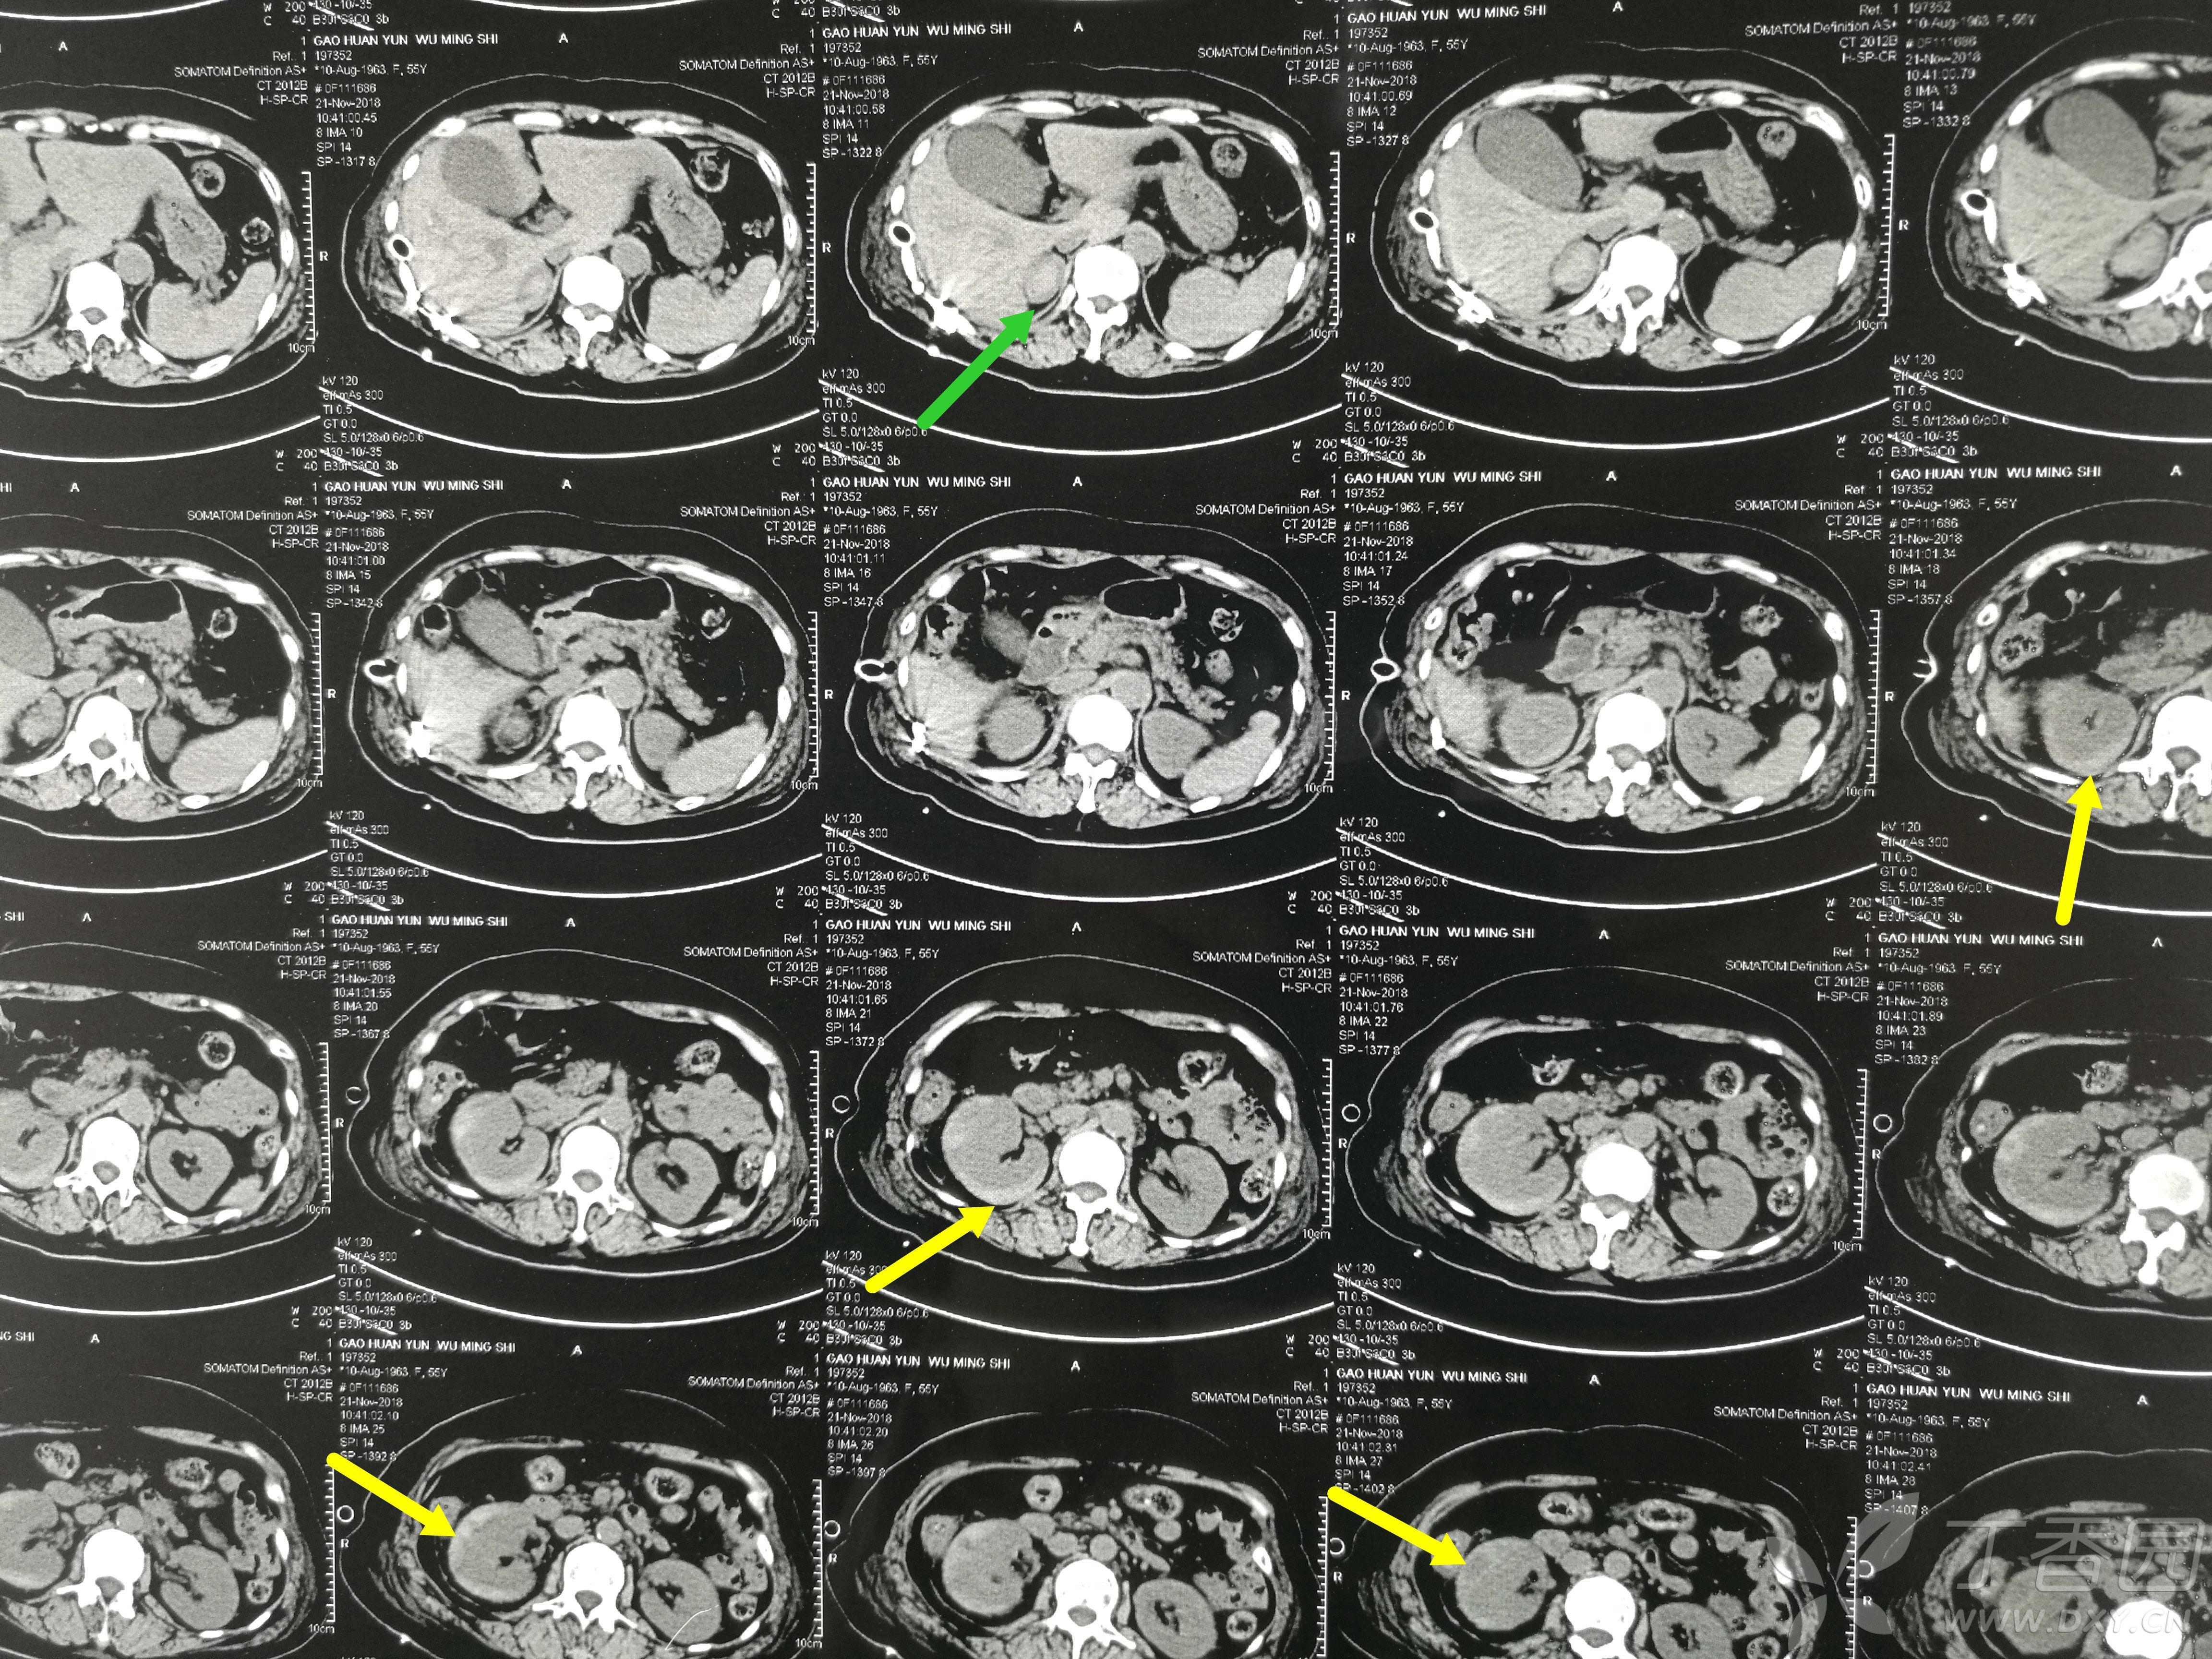

无血尿,入院查ct提示:黄箭头所指为右肾包膜下高密度影,考虑血肿;绿